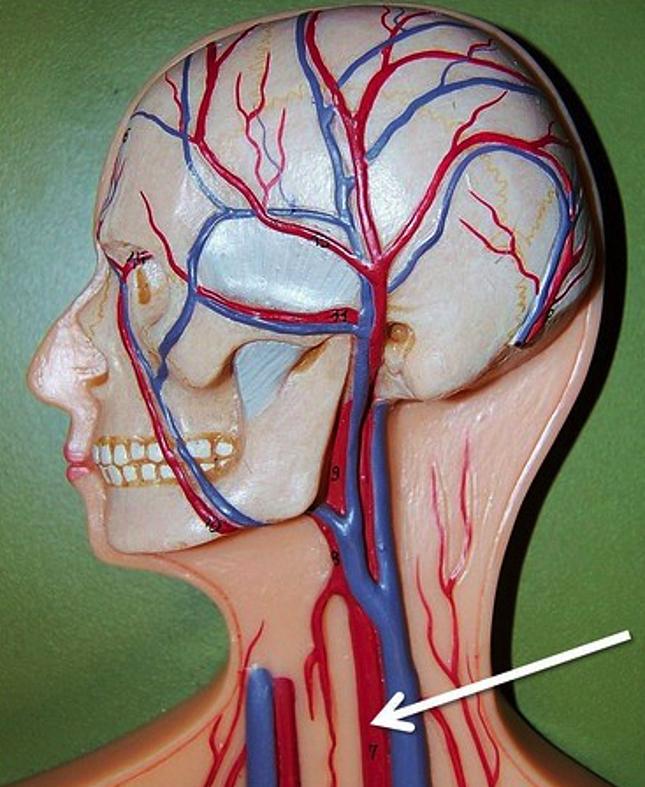

Анатомия внутренней яремной вены: КТ изображения

Раздел: Другие животные